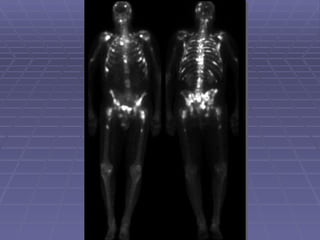

Acute Osteomyelitis   Early plain radiography signs of osteomyelitis are non-specific. 3-phase bone scan is usually the procedure of choice to differentiate between osteomyelitis and cellulitis.

Acute Osteomyelitis-cont.. If first and 2nd phases are positive (hyperemia) with normal third phase, diagnosis would be cellulitis. In acute osteomyelitis all 3-phases are positive (hyperemia and osteoblastic process in the bone).

Acute Osteomyelitis-cont.. Iffirst and 2nd phases are positive (hyperemia) with normal third phase, diagnosis would be cellulitis. In acute osteomyelitis all 3-phases are positive (hyperemia and osteoblastic process in the bone).

Whole Body Bone Scan